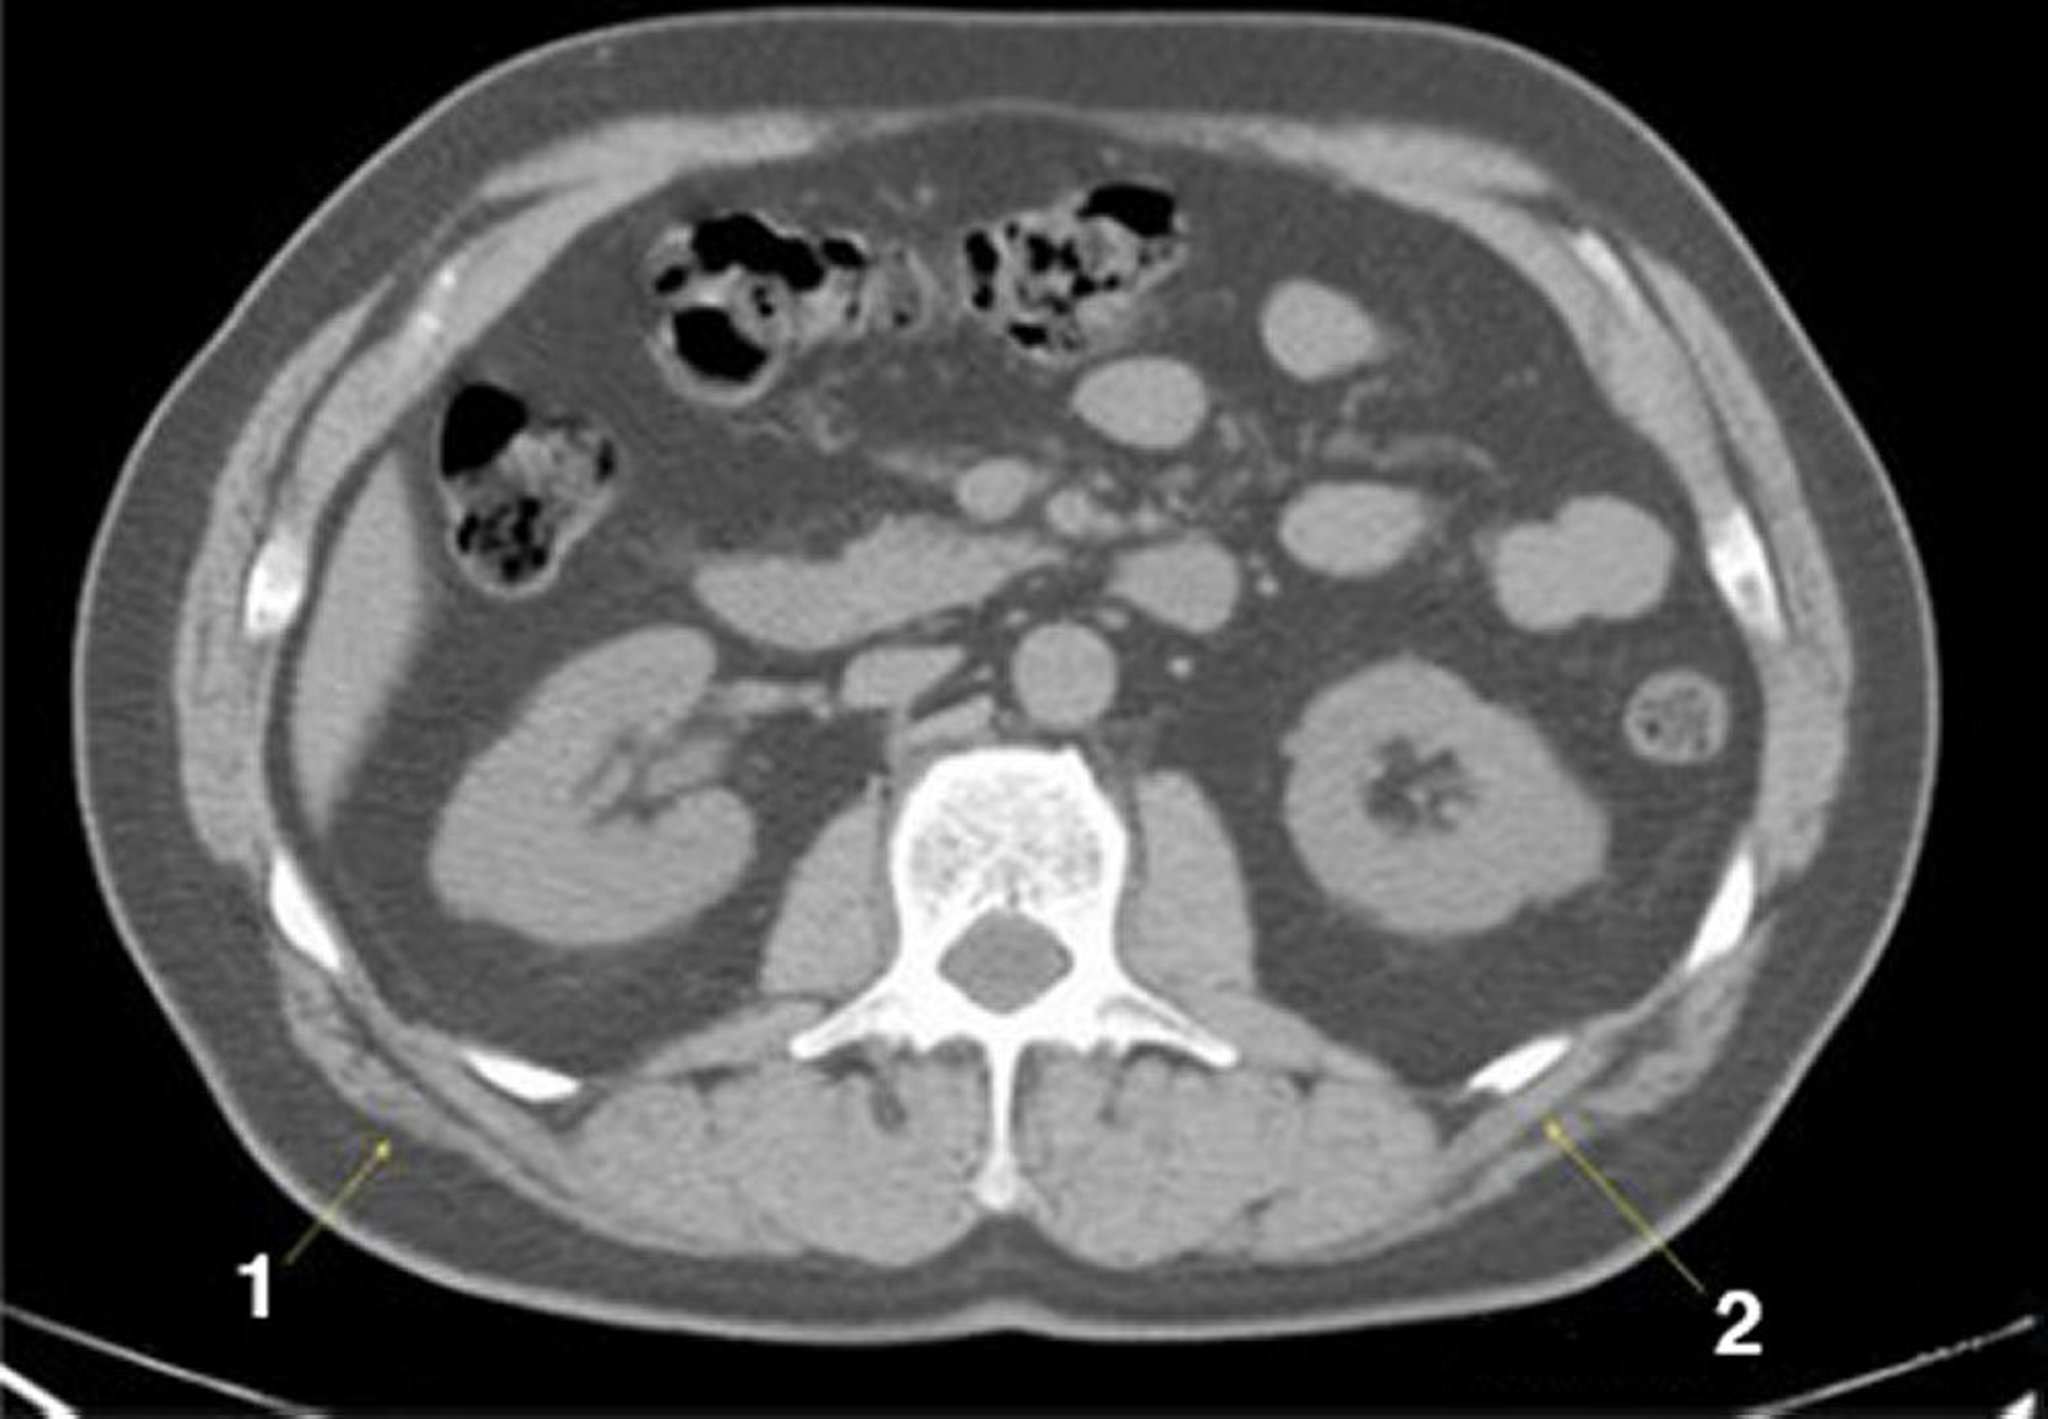

Tomografía computarizada sin contraste de abdomen y pelvis que muestra anatomía normal (corte 15)

1 = latissimus dorsi; 2 = serratus posterior.